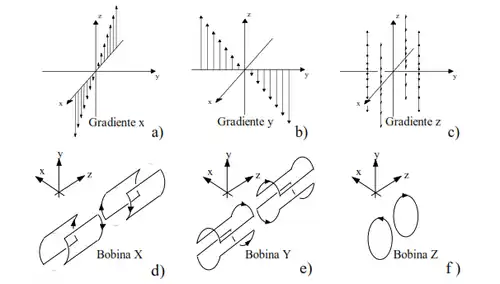

- Gradientes de campo magnético

O novo elemento codificador do sinal é um campo magnético não homogêneo e variável no tempo. Este campo tem uma componente paralela ao B0 (eixo z) com dependência espacial linear, que é sobreposta ao mesmo. Para poder representar as 3 orientações espaciais de um objeto, são utilizados os gradientes de campo nas 3 direções ortogonais.

As bobinas encarregadas de gerar esta distribuição de campo são denominadas bobinas de gradiente. Desta maneira, a componente z do campo resultante fica expressa como:

Assim, cada conjunto de spins localizados em uma posição diferente, terá uma frequência de precessão diferente, dada pela expressão:

A frequência de precessão não é a única variável que passa a ter uma dependência espacial. Após um dado tempo de aplicação de qualquer gradiente, o acúmulo de fase também será uma função da posição. Deste modo, estas duas variáveis formam as bases da codificação espacial.

O gradiente de campo introduzido corresponde ao termo .